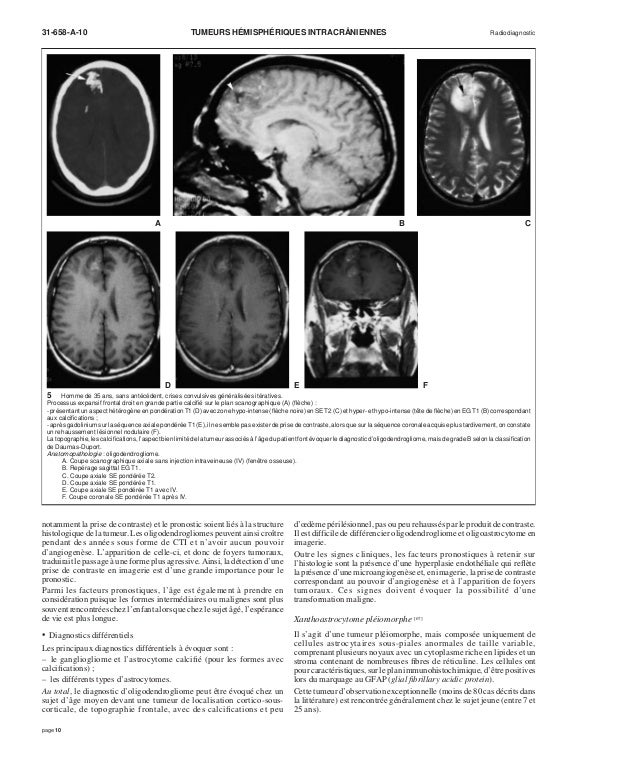

Quels sont les signes qui doivent alerter sur une éventuelle tumeur cérébrale ?. Chapitre 7 Tumeurs cranioencéphaliques tumeurs intraaxiales JL Dietemann, A Bogorin, M Abu Eid, M Koob Plan du chapitre INTRODUCTION TUMEURS CÉRÉBRALES PRIMITIVES MÉTASTASES CÉRÉBRALES Introduction Les tumeurs cranioencéphaliques sont classées en deux grands groupes, les tumeurs intraaxiales et les tumeurs extraaxiales. Interview d'Antoine Seyve, post doctorant, interne au sein du service de neurooncologie de la PitiéSal.

Tumeurs Hemispheriques Intracraniennes